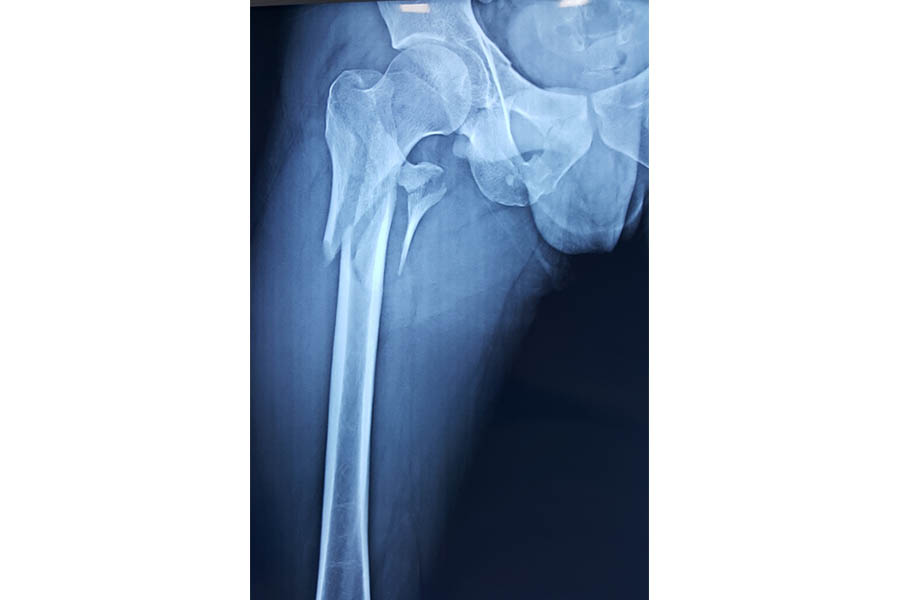

Total Hip Replacement